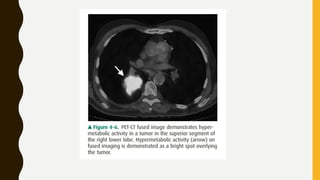

PET SCAN

• It’s a functional imaging technique that uses radiotracers to

visualise and measure change in metabolic processes.

• Technique with FDG(fluorodeoxyglucose) an analogue of glucose.

Reflects tumor cell metabolism.

• Pet imaging with oxygen 15 indirectly measures blood flow to the

brain